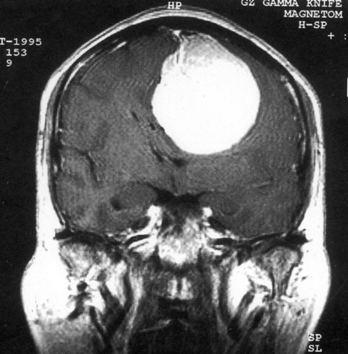

问题 病历摘要:??患者,男,40岁。发作性左下肢抽搐1年余,每次发作3~5分,每周发作1~2次。每次发作后感左下肢乏力,约半日后可自行恢复。既往身体健康。体检:神清,头顶部偏右有局限性骨性隆起(1.5×1.5cm),左鼻唇沟稍浅,伸舌居中。感觉、运动无明显异常。左浅反射减退,左下肢腱反射稍亢进,左Babinski征(-)。 下列对该患者的临床特点分析哪些是正确的?

选项 A.有Jackson癫痫发作 B.有Todd氏麻痹 C.有精神运动性癫痫发作 D.右中央前回可能有刺激性病灶存在 E.右中央后回可能有破坏性病灶存在 F.有失张力发作 G.右锥体束征(+) H.有颅内高压表现

答案 ABDG

解析 ABDG